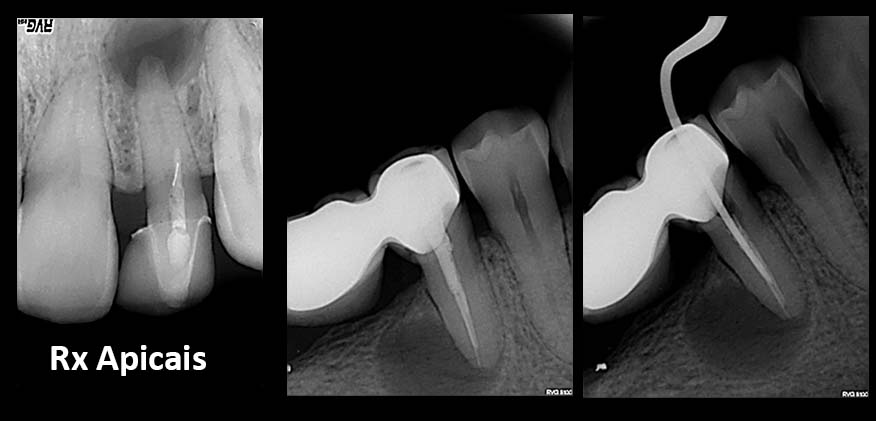

2. Radiografias

Tratamentos urgentes serão executados se necessário, como no caso à esquerda.